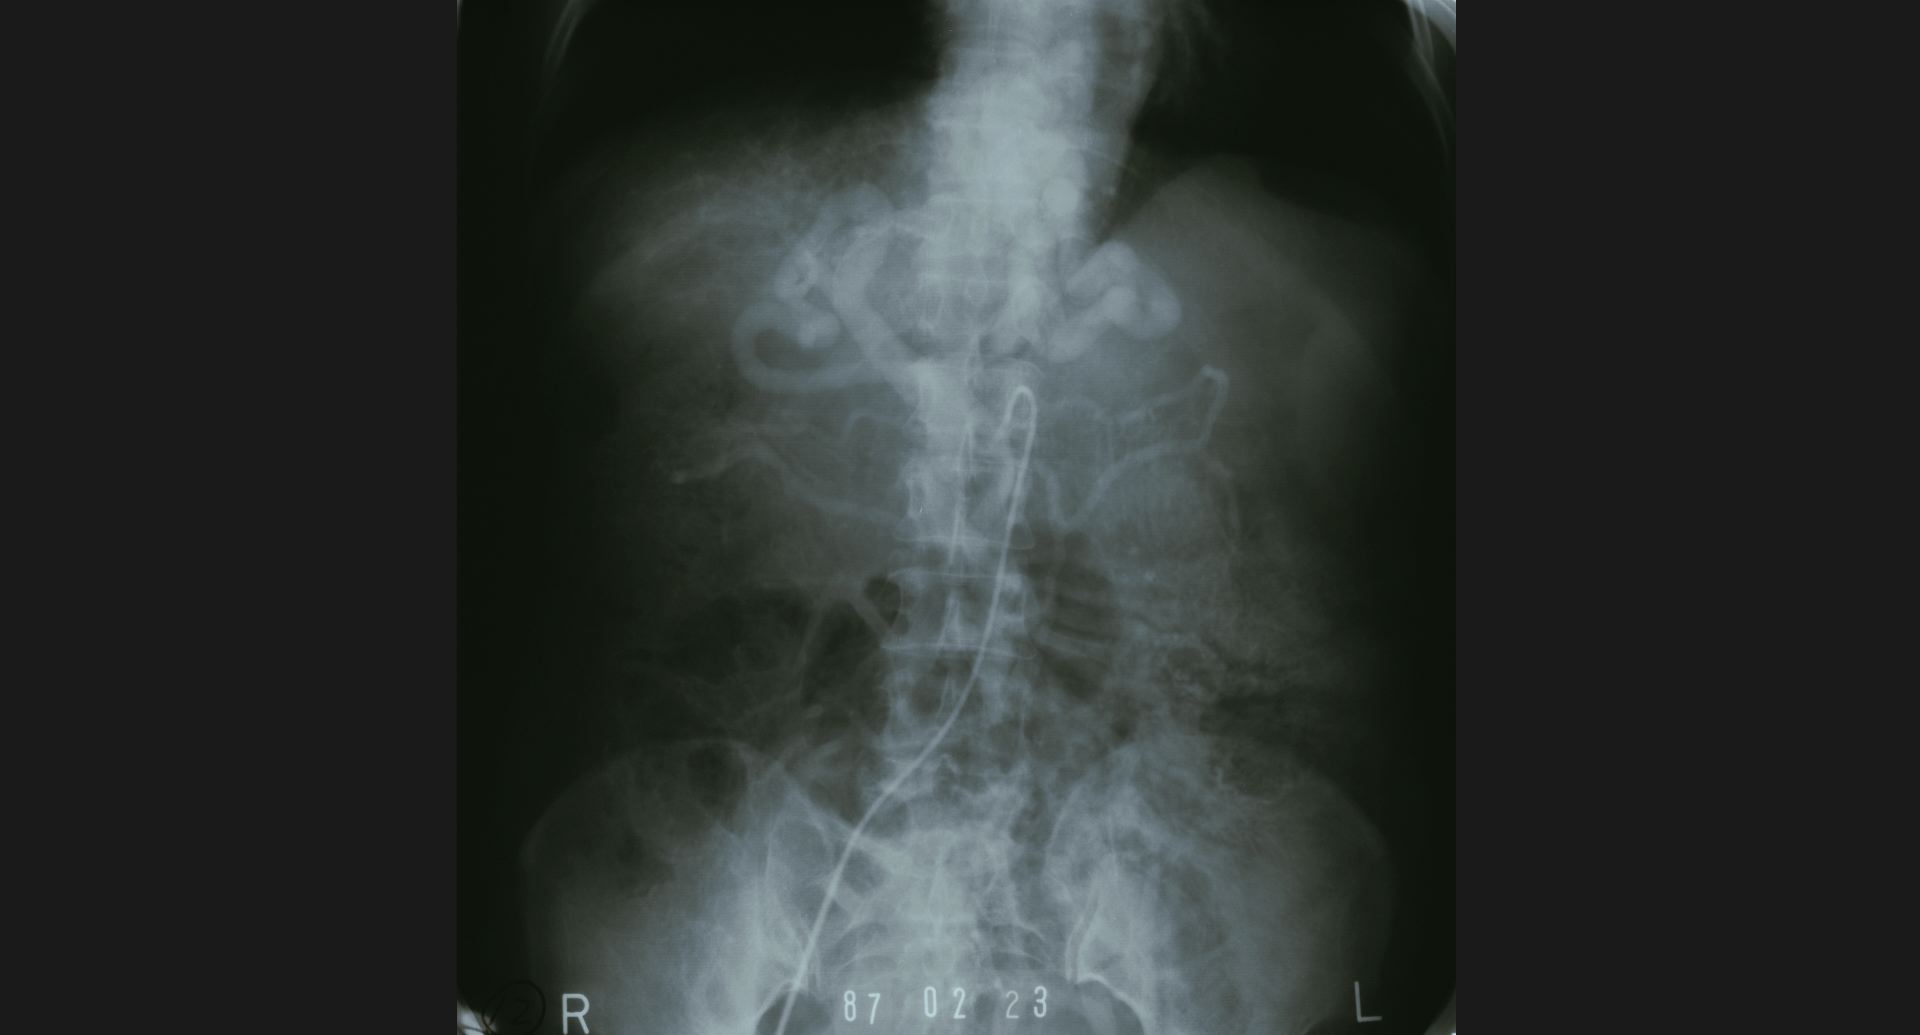

fig.16(93KB) :Osteoblastic metastases (骨盤)